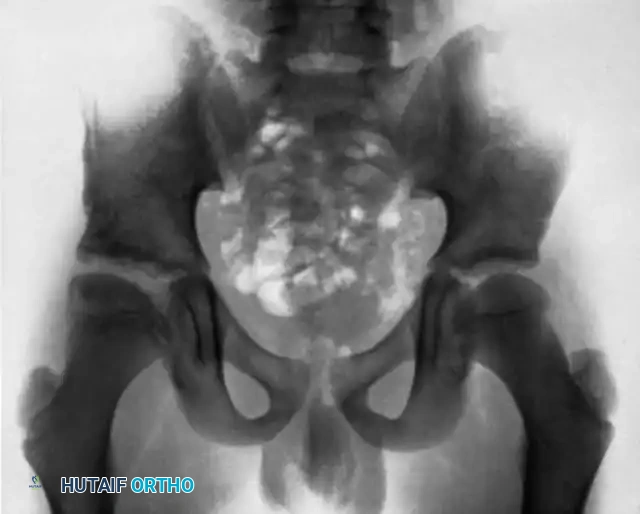

The Hip and Pelvis

Tuberculosis of the hip frequently affects children and young adults. The disease begins in the acetabular roof or the femoral head, rapidly progressing to joint space narrowing and severe destruction. A classic late-stage presentation is the "wandering acetabulum," where superior and medial migration of the femoral head occurs due to progressive bone loss.

In cases of severe destruction, nonoperative management leads to painful, fibrous ankylosis in a non-functional position (flexion, adduction, and internal rotation). Surgical intervention involves radical debridement. In modern practice, a two-stage total hip arthroplasty (THA) is often favored over hip arthrodesis to maintain mobility, provided the infection is medically cleared.

Pelvic and sacroiliac (SI) joint tuberculosis often presents with lower back pain radiating to the gluteal region, mimicking sciatica. Radiographs and CT scans will show erosions of the SI joint margins. Treatment is primarily medical, but large presacral or iliopsoas abscesses require CT-guided percutaneous drainage or open surgical debridement.